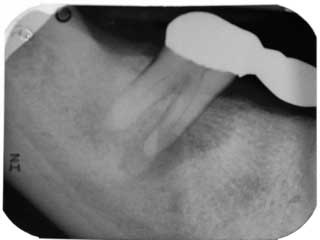

A 52-year-old female patient presented to our office for consultation on tooth No. 31 with the chief complaint: “My dentist says I need to have my tooth pulled, but I want to see if I can save it.” Medical history was noncontributory. Patient had a bridge placed more than five years ago from Nos. 29 through 31. She had a history of mild discomfort in the area of No. 31, but had not had any serious problems until two months prior when a fistula had developed. She visited her dentist, who took radiographs and deemed tooth No. 31 fractured and nonrestorable. She had been referred to a periodontist for extraction of No. 31 and implant placement in areas of No. 30 and No. 31. Having been to our office for previous endodontic therapy, the patient returned for a second opinion.

Clinical evaluation revealed a draining fistula on the buccal aspect of tooth No. 31. Endodontic testing revealed tooth No. 31 had no response to cold, no pain to percussion, 7-8 mm probing depths on its distal aspect, and pain on palpation. All other teeth in the quadrant tested normal. The diagnosis was pulpal necrosis with chronic periradicular abscess. The patient was advised that the prognosis was guarded, but if she wanted to try to save the tooth, we could try.